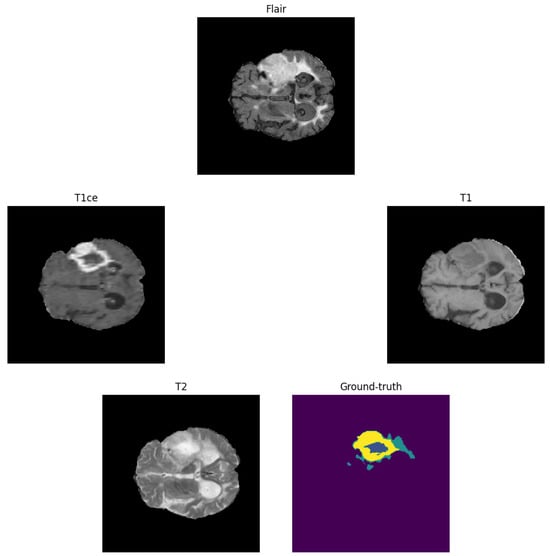

3.1. Image Pre-Processing

3.3. Proposed Brain Tumour Segmentation